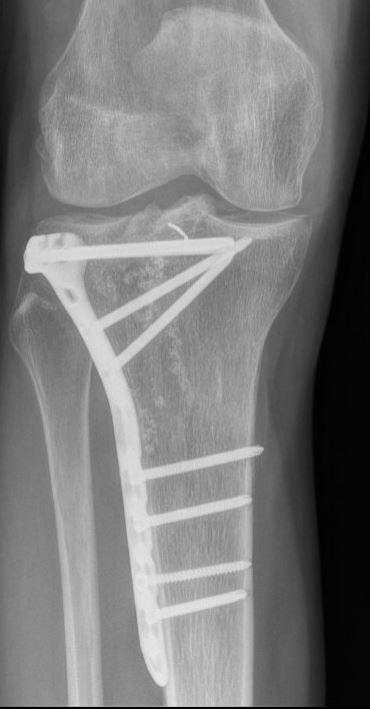

Operatie

Indien u geopereerd moet worden, zal dat meestal gebeuren met een plaat en schroeven om de breukdelen stevig aan elkaar vast te zetten en te verbinden aan de rest van het scheenbeen. Soms zijn hiervoor zelfs meerdere platen nodig. In een enkel geval is het gebruik van alleen schroeven voldoende. Welke operatie u precies krijgt, is afhankelijk van de eigenschappen van de breuk, de toestand van de huid, spieren, zenuwen en bloedvaten en de voorkeur van uw traumachirurg.